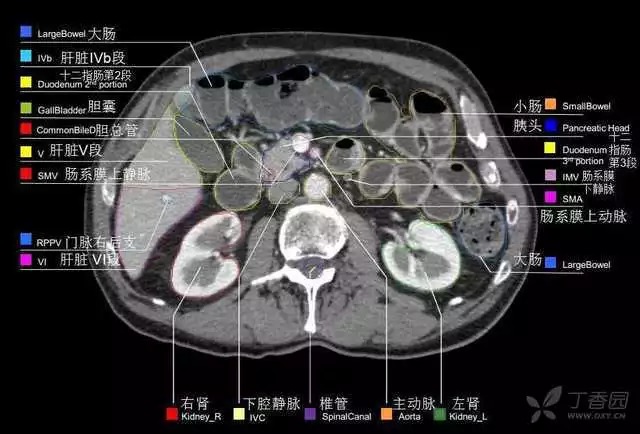

腹部肝脏高清CT断层的图谱

全腹部高清CT图谱,淋巴结彩色图谱,血管解剖图谱大汇总!

肝段,肝内管道的分布规律

美国放射学会ACR官网,对肝脏的区域和节段解剖学概述